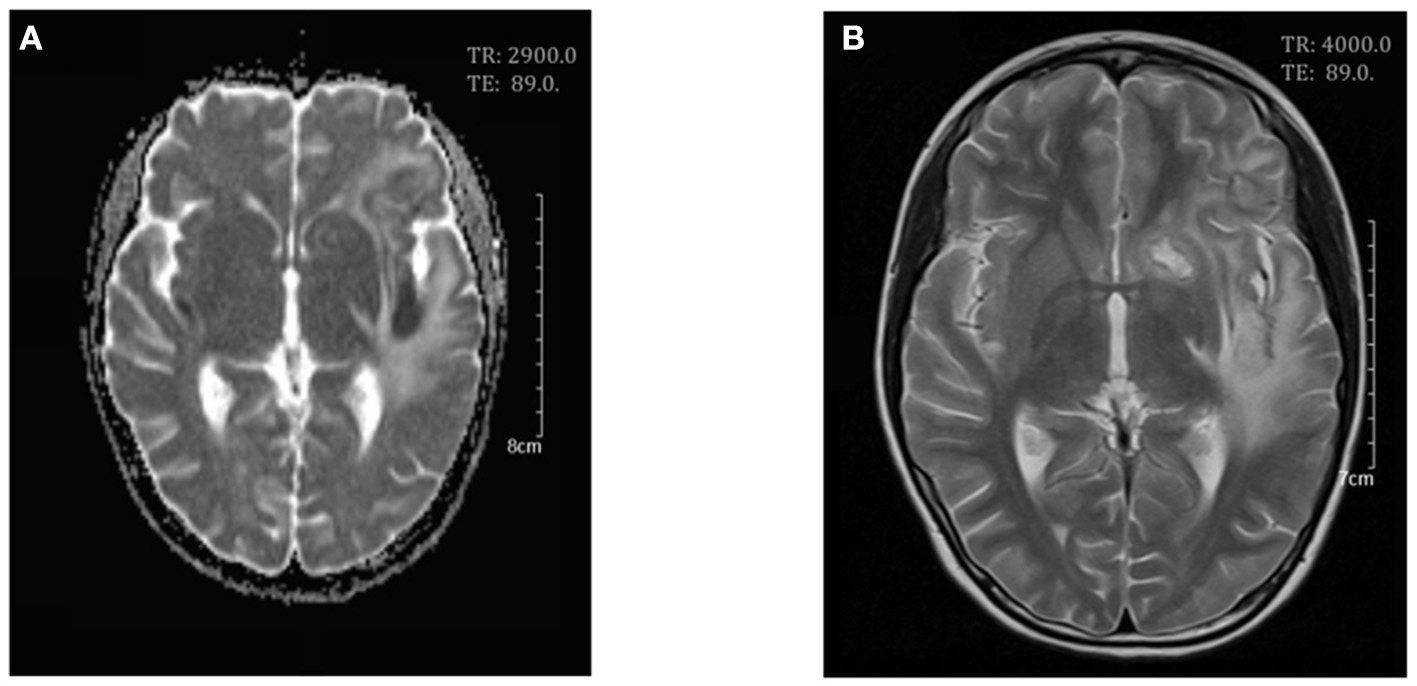

On day 7 after admission the patient appeared weak and ill, then the next day she exhibited dizziness, drowsiness, apathia, and dysarthria, and her temperature reached 37.9°C. The patient was given high-dose methylprednisolone pulse therapy (30 mg/kg/day) for 3 days. On day 9 the second cerebral MRI showed rapid progress (Figure 2), with multi-focal abnormal signals mainly involving white matter (bilateral temporal, cerebellum, insular lobes, and basal ganglias; left frontal and parietal lobes; right corpus callosum). The signals were hyperintense on fluid-attenuated inversion recovery (FLAIR). Cyclophosphamide (8.5 mg/kg/day for 2 days) and intravenous immunoglobulin (2 g/kg) were initiated in the therapy. On day 10 the patient showed significant improvements in all clinical conditions, including the rashes. On day 13 the third MRI demonstrated small infarcts in the left lentiform nucleus, left frontal lobe, temporal lobe, insular lobe, parietal lobe, and right corpus callosum, revealed by decrease in apparent diffusion coefficient in the gray matter, and an increased swelling in the surrounding white matter (Figure 3). She was given intrathecal dexamethasone once a week for three times. The second pulse of high-dose methylprednisolone was administered 1 week after the first pulse. Cyclophosphamide and immunoglobulin were administered with an interval of 2 weeks. On day 25 she had a fourth MRI scan and achieved neuroimaging improvements (Figure 4). The patient was discharged on day 30, with prednisone and addition of hydroxychloroquine.

Figure 4

Cerebral magnetic resonance imaging on day 25. Axial T2-weighed scan (A) and apparent diffusion coefficient (ADC) maps (B) showed a decrease in white matter swelling.